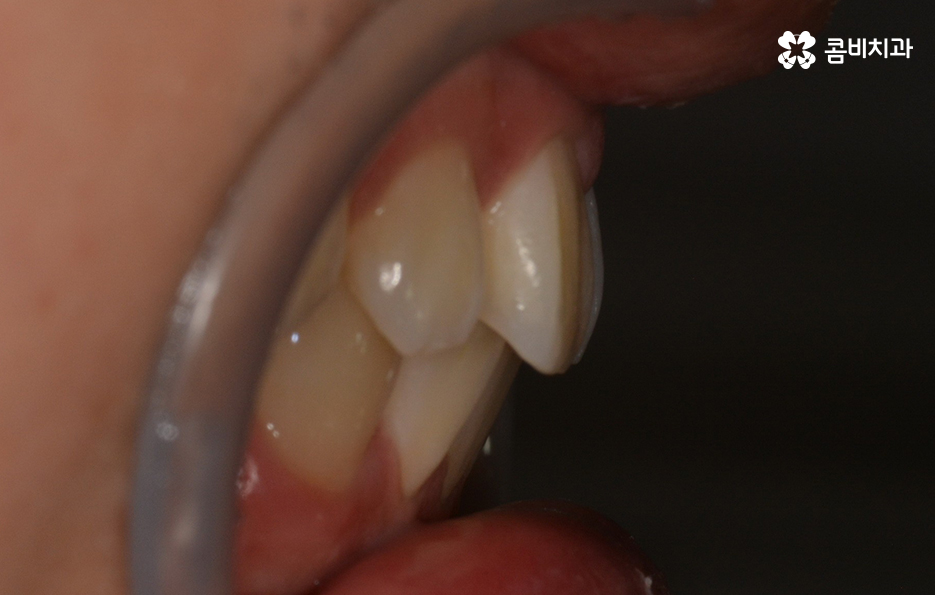

전체 치열과 교합은 큰 문제가 없는 편이나

앞니 정도가 벌어진 경우와 같이 제한적인 경우가 많습니다.

위 사례의 경우 유독 앞니 위주로 치아가 벌어져 있는 상태이며

옆모습의 경우에도 비교적 양호한 상태입니다.

치아부분교정은 위 사례와 같이 대부분 앞니 6개의 치아에

부분적으로 교정 장치를 부착하여 진행이 되며